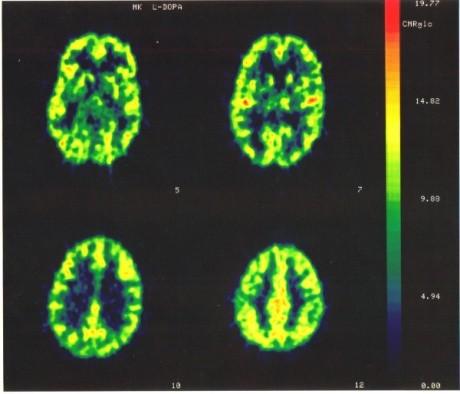

m-d-mark-d-kelland-personality-theory-in-a-cultura-5.jpg

In these figures, adapted from research conducted by the author (Kelland et al., 1989), we see two correlations reported in an actual study. In the figure on the left, we can see a significant positive correlation between the firing rate of dopamine neurons in the rat brain and the dose of the drug quinpirole needed to inhibit those cells. In the figure on the right, we can see that this correlation is eliminated (i.e., the dose of quinpirole needed is not related to the firing rate of the cell) following administration of the drug MDMA (more commonly known as Ecstasy!). [Image by Mark Kelland]